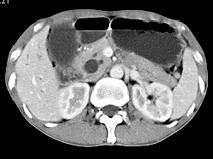

问题 男,48岁,进行性黄疸,发热,腹胀,影像检查如图,最佳的诊断是 ( )

选项 A、十二指肠乳头癌 B、胰头癌 C、胆总管结石 D、胆总管癌 E、胆总管囊肿

答案 A